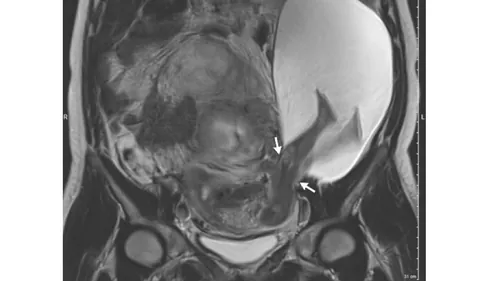

The case was about a 33-year old woman who was 22 weeks pregnant. Although she appeared to have no symptoms at first glance, routine ultrasound detected something unexpected. Subsequent magnetic resonance imaging showed that her uterine wall had a 2.5-centimeter-long (1 inch) rupture and the amniotic sac had herniated, letting the fetus’s abdomen and legs to poke through.